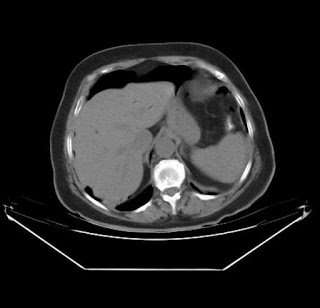

Las perforaciones postCPRE, por suerte son muy poco frecuentes (0.3-1.2 % de todas las CPRE), aunque pueden llegar a tener una mortalidad cercana al 30 %. Su detección y manejo precoces son crucieles en el pronóstico. La mayoría de las perforaciones están relacionadas con la esfinterotomía, sobre todo las de precorte, aunque en los últimos años las perforaciones por guía están aumentando en frecuencia. Otros factores asociados son la dilatación de estenosis biliares y pancreáticas, la presecia de una dilatación importante del conducto biliar, un procedimiento complejo y prolongado, la presencia de un divertículo yuxtapapilar y quizás la esfinteroplastia con balón CRE. Las perforaciones que se diagnostican tras la CPRE se suelen sospechar porque se presentan de forma mas precoz que las pancreatitis (PA) postCPRE, el dolor, la distensión abdominal con la presencia de peritonismo son mas llamativos que en ésta. El paciente suele tener repercusión sistémica con la presencia de taquicardia e hipotensión, así como una leucocitosis precoz con neutrofilia mas intensa que en las PA. Por el contrario, los niveles de amilasa suelen ser normales o con menor elevación que en la PA. La prueba diagnóstica crucial es el TAC abdominal urgente, que demostrará la presencia de retroneumoperitoneo con o sin neumoperitoneo en el espacio perirrenal y perihepático. Si el paciente tiene una situación clínica estable, es muy importante no precipitarse con los hallazgos del TAC y no intervenir de forma precoz a los pacientes ya que podemos inducir una morbimortalidad mucho mayor (agravamos el problema sin encontrar la microperforación en muchas ocasiones). El tratamiento conservador (SNG, ABS de amplio espectro y en ocasiones NPT) suele ser suficiente. Solamente cuando el deterioro clínico del paciente es evidente (acentuación de la peritonitis, leucocitosis > 15000 con intensa neutrofilia, fiebre > 38º C y fundamentalmente deterioro hemodinámico -FC> 100 lpm, TAS < 100) o aparecen colecciones en el TAC, habrá que intervenir.

La conclusión práctica es que en estos casos, la situación clínica del paciente es crucial y siempre nos tiene que marcar la actuación clínica. En CPRE prolongadas, donde se introduce mucho aire en el tubo digestivo, éste es capaz de disecar las paredes del duodeno en la zona de la esfinterotomía y provocar neumoperitoneo asintomático-paucisíntomático sin ninguna trascendencia clínica. Están descritos casos de retroneumoperitoneo en el 24 % de todas las esfinterotomías sin ninguna repercusión clínica (Significance of retroperitoneal air after endoscopic retrograde cholangiopancreatography with sphincterotomy.Am J Gastroenterol. 1999 May;94(5):1267-70). Incluso hay casos de aire libre intraperitoneal, neumomediastino y enfisema subcutáneo sin existir datos clínicos y analíticos que sugieran una perforación. Toda precaución tanto en exceso como en defecto puede tener consecuencias muy negativas para el paciente.

Se expone el caso de una paciente, donde tras analizar la evolución clínica de forma estricta tras la CPRE con esfinteroplastia, es muy posible que desde el primer momento, no se tratara de una micorperforación sino de la simple presencia de aire libre intraperitoneal.